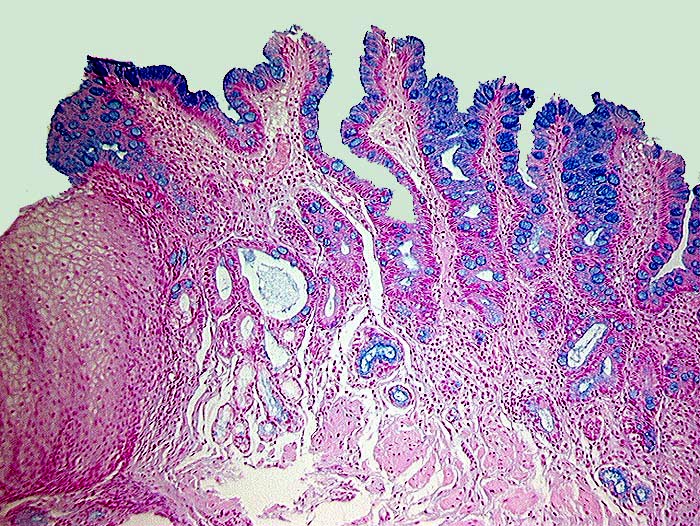

PathoPic ID 9 - Barrett Schleimhaut ohne intraepitheliale Neoplasie

Barrett Schleimhaut ohne intraepitheliale Neoplasie

Metaplasie / Heterotopie

Oesophagogastrischer Uebergang

Oesophagus, Magen

Zwischen erhaltenen Inseln normaler Ösophagusschleimhaut findet sich spezialisiertes metaplastisches Epithel mit alcianblauen Becherzellen.

Endobrachyösophagus

Histologie